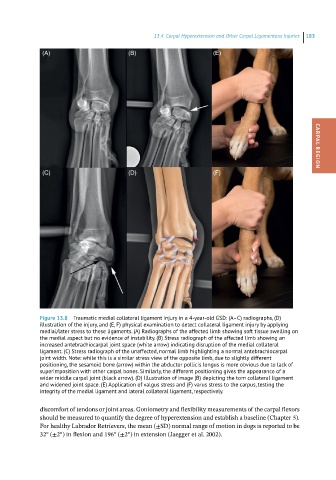

Figure 13.8 Traumatic medial collateral ligament injury in a 4-year-old GSD: (A–C) radiographs, (D)

illustration of the injury, and (E, F) physical examination to detect collateral ligament injury by applying

medial/later stress to these ligaments. (A) Radiographs of the affected limb showing soft tissue swelling on

the medial aspect but no evidence of instability. (B) Stress radiograph of the affected limb showing an

increased antebrachiocarpal joint space (white arrow) indicating disruption of the medial collateral

ligament. (C) Stress radiograph of the unaffected, normal limb highlighting a normal antebrachiocarpal

joint width. Note: while this is a similar stress view of the opposite limb, due to slightly different

positioning, the sesamoid bone (arrow) within the abductor pollicis longus is more obvious due to lack of

superimposition with other carpal bones. Similarly, the different positioning gives the appearance of a

wider middle carpal joint (black arrow). (D) Illustration of image (B) depicting the torn collateral ligament

and widened joint space. (E) Application of valgus stress and (F) varus stress to the carpus, testing the

integrity of the medial ligament and lateral collateral ligament, respectively.